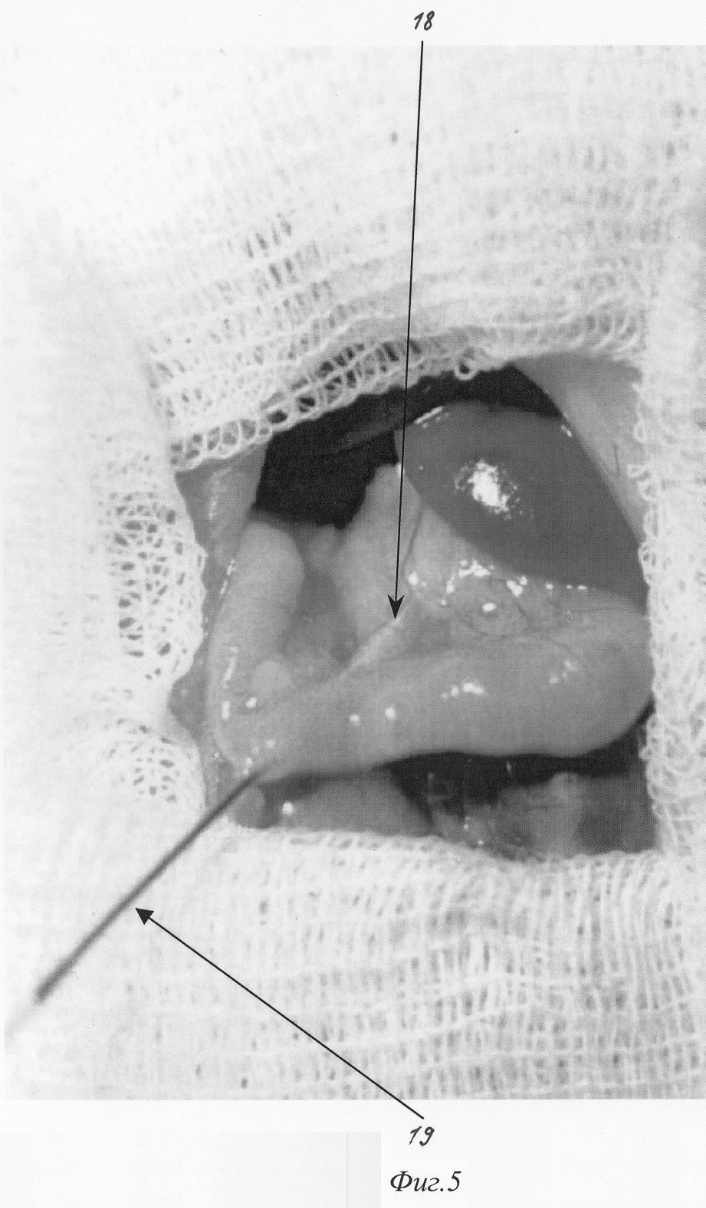

Изобретение относится к медицине, а именно к экспериментальной хирургии, и может быть использовано для моделирования острого деструктивного панкреатита у крыс. Близким решением является способ моделирования, разработанный Aho HJ, Koskensalo SM, и Nevalainen TJ, описанный в статье Experimental pancreatitis in the rat. Sodium taurocholate-induced acute haemorrhagic pancreatitis. Scand J Gastroenterol 15: 411-416, 1980. Который заключается в трансдуоденальной катетеризации общего желчного протока и введение таурохолата натрия (0,4 мл 4% раствора) в общий желчный проток и протоки поджелудочной железы. При использовании данного способа моделирования острого деструктивного панкреатита патогенетические механизмы, лежащие в основе большого количества летальных исходов, отличаются от таковых при развитии острого панкреатита в клинике. Так, таурохолат, являясь гемолитическим ядом, при применении в вышеуказанных концентрациях вызывает внутрисосудистый гемолиз. Другим отрицательным свойством данной модели является невозможность влияния на площадь панкреонекроза. Немаловажным фактором, влияющим на интрапанкреатическую активацию ферментов поджелудочной железы, является уровень рН в ее протоковой системе, что никак не учитывается в данной модели. Задачей изобретения является разработка модели острого панкреатита, наиболее оптимально соответствующей патогенетическим механизмам, имеющим место при развитии острого панкреатита у человека, позволяющей регулировать площадь панкреонекроза, а также снижение летальности, обусловленной гемолитическим действием вводимого в протоки раствора. Поставленная задача решаются тем, что для моделирования острого деструктивного панкреатита вместо раствора таурохолата натрия мы используем трансдуоденальное внутрипротоковое введение специальной буферной системы, содержащей соль желчной кислоты при оптимальной для интрапанкреатической активации ферментов рН. Для возможности управления площадью панкреонекроза мы используем различное наложение (дистальнее или проксимальнее места впадения добавочного протока поджелудочной железы в общий желчный проток) лигатуры, что обеспечивает развитие тотального или субтотального панкреонекроза. Изобретение поясняется фигурами: – на фиг.1 изображено строение протоковой системы крысы (1); – на фиг.2 изображено строение протоковой системы крысы (2); – на фиг.3 изображен первый этап моделирования (срединная лапаротомия); – на фиг.4 изображен второй этап моделирования (выведение органов в рану); – на фиг.5 изображен третий этап моделирования (пункция двенадцатиперстной кишки и катетеризация общего желчного протока); – на фиг.6 изображен пример наложения турникетов для воспроизведения субтотального панкреонекроза; – на фиг.7 изображен пример наложения турникетов для воспроизведения тотального панкреонекроза; – на фиг.8 изображен пятый этап моделирования – ушивание лапаротомной раны. Способ осуществляется следующим образом. Операция проводится с соблюдением правил асептики и антисептики под эфирным наркозом. После обработки операционного поля послойно вскрывается брюшная полость (верхнесрединная лапаротомия) на протяжении 2-3 см (фиг.3). Операционное поле отгораживается стерильными салфетками. При вскрытии брюшной полости в рану выводится петля двенадцатиперстной кишки (фиг.2. 12, фиг 4). В гепатодуоденальной связке определяется общий желчный проток крысы диаметром 0,3-0,5 мм (фиг.2. 11, фиг.4. 16 ). На расстоянии приблизительно 1,5 см от ворот печени (фиг.2. 10) в общий желчный проток по задней поверхности впадает главный панкреатический проток (фиг.2. 9), который собирает секрет от желудочной и селезеночной частей поджелудочной железы и имеет диаметр приблизительно около 0,2-0,3 мм, что лучше видно при рассечении связки аналоги lig. gastrocolicum и отведении желудка кверху (фиг.1). При этом мы увидим дистальную часть общего желчного протока (фиг.1. 2), впадающий в него главный панкреатический проток (фиг.1. 3), желудочную часть поджелудочной железы (фиг.1. 7), прилежащую к задней стенке желудка (фиг.1. 4), и селезеночную часть поджелудочной железы (фиг.1. 6), прилежащую к воротам селезенки (фиг.1. 5). Также при этом доступе можно увидеть и дуоденальную часть поджелудочной железы (фиг.1. 8), дренирующуюся дополнительным протоком (фиг.1. 1), который впадает в общий желчный проток по задней его поверхности на расстоянии около 0,5 см от места вхождения общего желчного протока в стенку двенадцатиперстной кишки. Место впадения дополнительного панкреатического протока в общий желчный проток можно увидеть и при выведении ДПК, как это показано на фиг.2. 19. Интрамуральный отдел общего желчного протока (фиг.2. 14) открывается в просвет ДПК, что можно увидеть через стенку кишки (фиг.2. 14, фиг.4. 17). Найдя место впадения общего желчного протока от него отступают около 0,5 см в этом месте производят пункцию двенадцатиперстной кишки зондом, диаметром 0,3 мм (фиг.5. 19), который через большой дуоденальный сосочек проводится в общий желчный проток до середины расстояния между местами впадения панкреатических протоков (фиг.5. 19). После этого на общий желчный проток накладывается два турникета. Один выше места впадения основного панкреатического протока (фиг.6. 20, фиг.7. 22), второй, в зависимости от того, какую форму панкреатита необходимо воспроизвести (тотальную или субтотальную), выше (фиг.6. 21) или ниже (фиг.7. 23) места впадения добавочного протока поджелудочной железы. Турникеты затягивают. В проток при помощи насоса для микроинфузий вводят 0,3 мл буфера (содержащего 0,3 г трис-гидроксиметил-аминометана и 0,6 г дезоксихолата натрия в 100 мл при рН 8,8) при скорости потока 0,07 мл в минуту. Турникеты с протоков снимают спустя минуту после прекращения введения буфера и удаляют катетер из протока. После создания модели органы погружаются в брюшную полость. Убираются отгораживающие салфетки. Брюшная полость послойно ушивается отдельными шелковыми швами (фиг.8). Рана обрабатывается раствором антисептика. Пример конкретного применения. Исследование проведено на 100 самках крыс линии Вистар массой 200 г. С целью подтверждения наличия острого деструктивного панкреатита производилось морфологическое исследование образцов поджелудочной железы на сроке 12 часов (как наиболее информативного срока). Образцы поджелудочной железы забирались, фиксировались в 10% растворе нормального формалина, обезвоживались, заливались в парафин, готовились парафиновые срезы, которые затем окрашивались гематоксилин-эозином. Также производилось исследование активности амилазы в сыворотке крови и перитонеальном экссудате амилокластическим методом со стойким крахмальным субстратом по Каравею. Кроме этого оценивалась летальность за первые сутки с момента моделирования. Полученные данные сравнивали с данным контрольной группы (интактные животные). Так, нормальные значения активности амилазы, вычисленные для нашей лаборатории, – 61,76 г/ч/л. После моделирования острого панкреатита описанным выше методом через 12 часов с момента моделирования активность амилазы сыворотки крови при тотальном панкреонекрозе достигает уровня 144,77±3,2 г/ч/л (р<0,01), а перитонеального экссудата 1237,36±7,4 г/ч/л (р<0,01) г/ч/л, при субтотальном панкреонекрозе 160,56±4,3 г/ч/л (р<0,01) и 1548,21±8,3 г/ч/л (р<0,01) – соответственно. При морфологическом исследовании получены следующие результаты: Макроскопическая картина при вскрытии брюшной полости и грудной клетки крысы после моделирования тотального панкреонекроза. При вскрытии в брюшной полости до 5 мл серозно-геморрагического выпота во всех отделах, гиперемия париетальной и висцеральной брюшины брыжейка тонкой кишки отечна, с множественными мелкими очагами стеатонекроза. Печень не увеличена, темно-вишневого цвета, поверхность ее гладкая, края долей заострены. Почки без видимой макроскопической патологии. Селезенка умеренно увеличена в размерах, темно-вишневого цвета. При вскрытии просвета желудка и ДПК определяются множественные мелкие (точечные) эрозии шоколадного цвета. Поджелудочная железа резко отечна с участками стеатонекроза размерами от 0,3 до 0,5 см в диаметре. В области желудочно-дуоденальной части имеются участки геморрагического панкреонекроза размерами до 0,3 см в диаметре. Отмечается отек забрюшинной клетчатки. При вскрытии грудной клетки определяется гиперемия плевры и небольшое количества светлого выпота. Поверхность легких гладкая, буроватого цвета с множественными точечными кровоизлияниями. Сердце без видимых макроскопических изменений. Морфологическое исследование поджелудочной железы (окраска гематоксилин-эозином увеличение 20 В дуоденальной части определяется зона тотального некроза с участками геморрагии, массивной нейтрофильно-макрофагальной инфильтрацией. Структура ацинусов не сохранена. В желудочной части имеет место крупноочаговый панкреонекроз с единичными участками геморрагии, клеточными структурами разрушенных панкреатоцитов, нейтрофильно-макрофагальной инфильтрацией. В зонах, удаленных от очагов некроза, структура ацинусов сохранена. В участках, примыкающих к зонам некроза, панкреатоциты имеют вакуолизированную цитоплазму, ядра неправильной формы. В селезеночной части определяются множественные центролобулярные некрозы. Имеется значительное количество ацинусов с сохраненной структурой, встречаются интактные островки Лангерганса. Макроскопическая картина при вскрытии брюшной полости и грудной клетки крысы после моделирования субтотального панкреонекроза. При вскрытии брюшной полости определяется до 3-4 мл серозно-геморрагического выпота. Париетальная и висцеральная брюшина гиперемирована во всех отделах. Брыжейка тонкой кишки отечна, с умеренным количеством мелких очагов стеатонекроза. Печень не увеличена, темно-вишневого цвета, поверхность ее гладкая, края долей заострены. На разрезе структура паренхемы не изменена, сосуды полнокровны. Селезенка умеренно увеличена в размерах, темно-вишневого цвета. Почки увеличены серовато-бурого цвета, на разрезе отчетливо просматривается кортикальный слой, темно-вишневого цвета с серым оттенком. При вскрытии просвета желудка и ДПК определяются множественные мелкие эрозии шоколадного цвета. Поджелудочная железа резко отечна с участками стеато и геморрагического панкреонекроза в желудочной части до 0,3 см в диаметре и участками стеатонекроза в парапанкреатической клетчатке. Дуоденальная часть железы отечна. При вскрытии грудной клетки определяется гиперемия плевры и небольшое количества светлого выпота. Поверхность легких гладкая, буроватого цвета с множественными точечными кровоизлияниями. Сердце без видимых макроскопических изменений. Морфологическое исследование поджелудочной железы (окраска гематоксилин-эозином увеличение 20 В дуоденальной части определяется интерстициальный отек с геморрагическим пропитыванием. Структура ацинусов сохранена. В желудочной части имеет место крупноочаговый панкреонекроз с единичными участками геморрагий, клеточными структурами разрушенных панкреатоцитов, нейтрофильно-макрофагальной инфильтрацией. В зонах, удаленных от очагов некроза, структура ацинусов сохранена. В участках, примыкающих к зонам некроза, панкреатоциты имеют вакуолизированную цитоплазму, ядра неправильной формы. В селезеночной части определяются множественные центролобулярные некрозы. Имеется значительное количество ацинусов с сохраненной структурой, встречаются интактные островки Лангерганса. При моделировании острого панкреатита летальность к первым суткам составила 80,6% при тотальном панкреонекрозе и 56,3% при субтотальном панкреонекрозе. В образцах крови, взятых при тотальном и при субтотальном панкреонекрозе, гемолиза не выявлено. Таким образом, поставленная задача достигнута, во первых, за счет уменьшения количества желчной кислоты в водимом в протоки растворе, во вторых, за счет поддержания рН вводимого раствора на оптимальном для активации ферментов уровне, в третьих, за счет наложения турникета до или после места впадения дополнительного протока поджелудочной железы в общий желчный проток и управления площадью некроза. В результате применения данного способа моделирования острого панкреатита развивается крупноочаговый некроз поджелудочной железы (тотальный или субтотальный), что, в свою очередь, приводит к: 1. Выявлению достоверных признаков развития острого панкреатита (морфологических и биохимических). 2. Возможности управления площадью некроза. 3. Снижению уровня летальности, связанной с гемолитическим действием солей желчных кислот. Формула изобретения